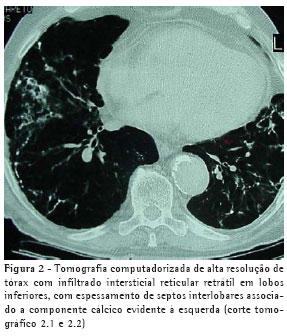

Um paciente do sexo masculino, de 75 anos de idade, ex-metalúrgico, tabagista de 50 maços-ano, procurou atendimento médico com dispnéia progressiva nos últimos quatro meses, que havia piorado havia uma semana e no momento do atendimento estava presente aos mínimos esforços. Relatava ainda dor torácica direita e tosse seca. Tinha antecedentes de diabetes melito, insuficiência renal crônica não dialítica, hipertensão arterial sistêmica e miocardiopatia isquêmica. Ao exame, apresentava-se dispnéico (freqüência respiratória de 30 incursões por minuto), taquicárdico (freqüência cardíaca de 120 batimentos por minuto), com estertores em velcro em bases, bulhas hipofonéticas e edema +/4+ em membros inferiores. A radiografia torácica (Figura 1) apresentou infiltrado intersticial retrátil em bases pulmonares, retificação de cúpulas frênicas com contornos mal-definidos, aumento difuso de transparência pulmonar em campos médios e superiores, imagem cardíaca aumentada, e aorta ectasiada e ateromatosa. A tomografia computadorizada de alta resolução do tórax (Figura 2) mostrou infiltrado intersticial reticular retrátil em lobos inferiores, com espessamento de septos interlobares associado a componente cálcico evidente à esquerda, enfisema centrolobular em lobos superiores, espessamento pleural esquerdo, aorta ectasiada e ateromatosa, e área cardíaca normal.

Os exames de imagem mostram infiltrados reticulares de densidade calcificada (tipo dendriforme) ao longo da distribuição broncovascular, comumente interpretados como cicatrizes, fibrose ou bronquiectasias, ou múltiplas calcificações subpleurais (tipo nodular) menores que 1 cm, confundidas com cicatrizes de doenças infecciosas.(4) Ossificações têm sido descritas histologicamente seis meses após sintomas congestivos, embora o processo possa não ser visto radiograficamente por três a cinco anos.(2) As lesões são indolentes, com progressão lenta ao longo dos anos, podendo permanecer sem modificações por muitos anos. Regressão não tem sido descrita.(4)